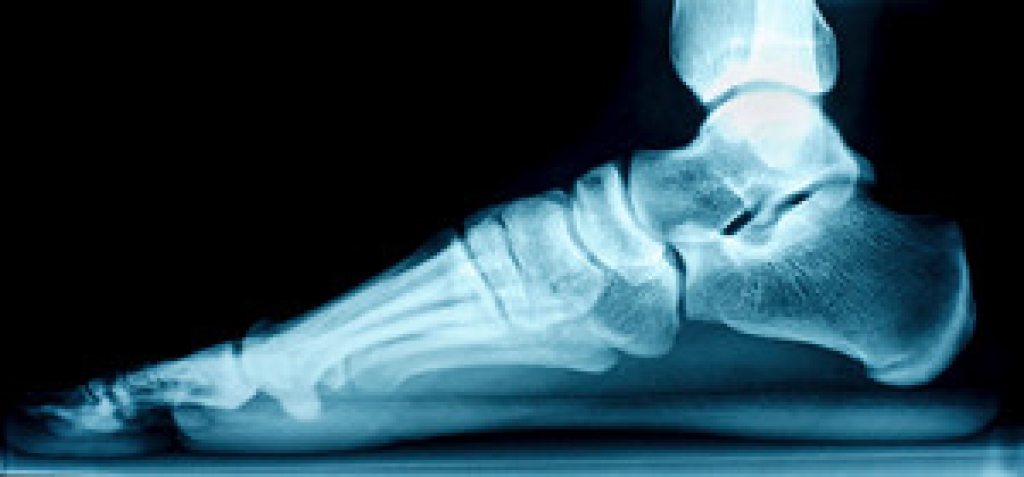

Foot surgery is sometimes necessary to treat a foot ailment. To learn more, contact one of our podiatrists of Lewis Wolstein, DPM, P.C. & Associates. Our doctors will assist you with all of your foot and ankle needs.

Foot and ankle surgery is generally reserved for cases in which less invasive, conservative procedures have failed to alleviate the problem. Some of the cases in which surgery may be necessary include: